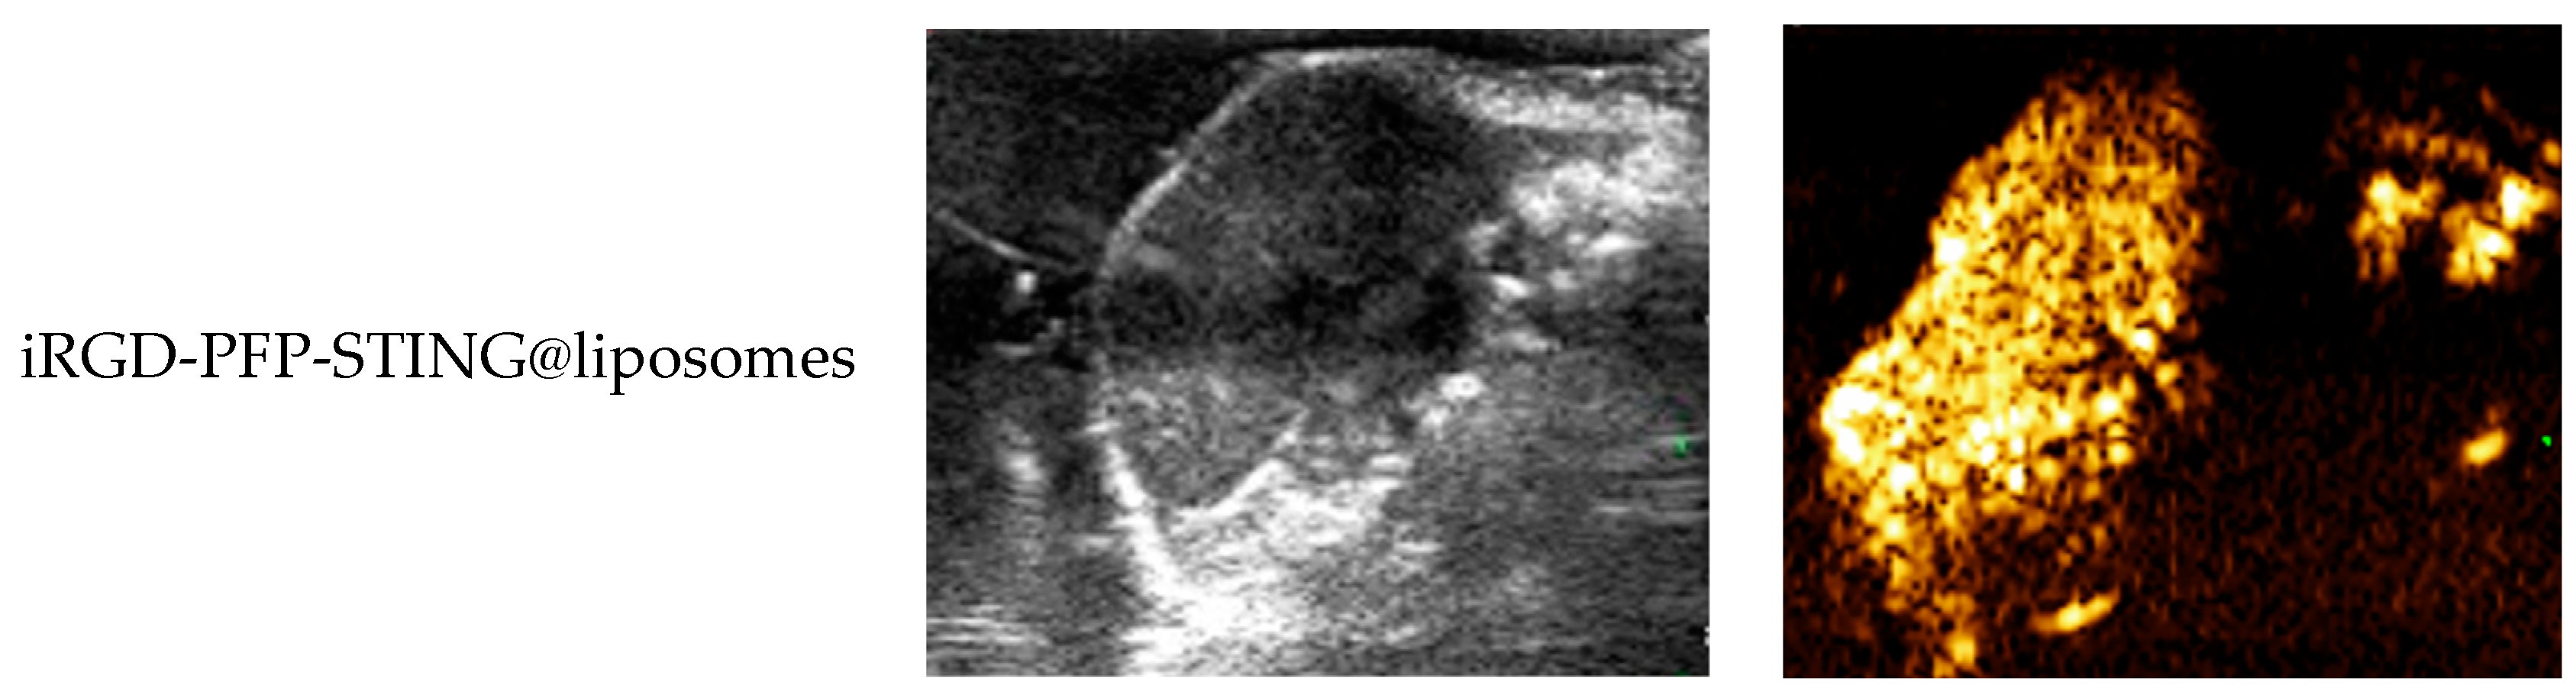

The ultrasound imaging of both targeted and non-targeted liposomes pre-ultrasound irradiation revealed no significant difference in US signal intensity between the two groups in both B- and CEUS-modes (p > 0.05) as shown in Figure 3. These images were captured using a US system (Esaote MyLab90, Florence, Italy) with the imaging parameters set to MI 0.08, TIB 0.3, and probe type LA523. Two factors were considered to induce the transition of liposomes into bubbles: heating (thermal factor) and ultrasound treatment (mechanical factors). The core of the nanodroplets used in this study was PFP, which has a boiling point of 29 °C at atmospheric pressure. However, according to Laplace pressure principles, droplets encapsulated in lipid shells can stabilize larger droplets and withstand greater pressure, which contributes to an increased evaporation temperature of the droplets [51,52]. This phenomenon suggests that nanodroplets facilitate infiltration into tumor tissues in vivo, enabling effective ultrasound imaging beyond the boundaries of tumor blood vessels. Therefore, they can enhance spatial contrast signals in both B-mode and CEUS-mode. The ADV was fixed at an ultrasound irradiation time of 3 min and an irradiation intensity of 3 W [38]. Following ultrasound irradiation, the liposomes underwent effective vaporization for ultrasound imaging, demonstrating the feasibility of using ADV simultaneously for both imaging and treatment purposes.

Figure 3.

(a) B-mode and CEUS-mode ultrasound images of PFP-STING@liposomes and iRGD-PFP-STING@liposomes before and after LIFU irradiation with 3 W for 3 min. Scale bar: 5 mm. (b) Echo intensity values of liposomes irradiated using LIFU. Data are represented as the mean ± SEM (n = 3, * p < 0.05, *** p < 0.001).

In Vivo Ultrasound Imaging

To evaluate the contrast-enhanced ultrasound effect of the liposomes in vivo, ultrasound imaging experiments were conducted on mice bearing 4T1 breast cancer xenografts. Following the injection of liposomes and subsequent ultrasound irradiation, a significant enhancement of the ultrasound signal was observed in the tumor region in both B-mode and CEUS-mode. Figure 5 illustrates the ultrasound images of the liposomes after destruction. Following 10 min of injection, exposure to LIFU at 3 W/cm2 in pulsed wave mode for three minutes resulted in the formation of hyperechoic regions in the tumor, as observed in both B-mode and CEUS-mode images. This finding indicated that phase transition of the nanoliposomes was successfully induced through ADV. In CEUS-mode, the ultrasound signal intensity in tumors treated with targeted iRGD liposomes was higher compared to non-targeted tumors. These results demonstrated that the developed liposomes enabled real-time monitoring and visualization of the tumor treatment area during drug therapy. In addition, the results confirmed that these liposomes exhibited targeted anti-tumor activity and could be effectively employed for ultrasound imaging, representing a promising therapeutic approach for tumor targeting.

Figure 5.

In vivo ultrasound imaging. The US and CEUS imaging pictures of PFP-STING@liposomes and iRGD-PFP-STING@liposomes obtained at 13 min post-injection. LIFU was applied for 3 min in 4T1 breast cancer xenograft model mice.